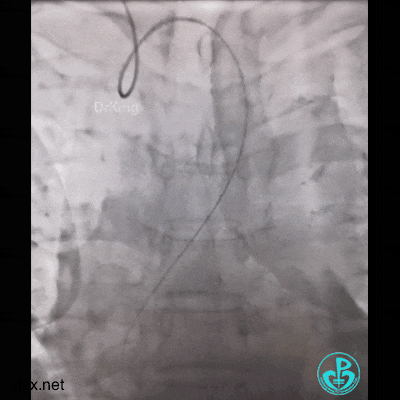

然而:锁骨下迷走,多次尝试TIG根本无法到位。

因为是心梗,患者持续胸痛,生命体征不稳,不再尝试,改腿。

然而,还是不能到位。

带的J-W转,突然血压没了,看下面,悲剧了。

糟糕,打折了,想解开,重新换管子。

结果上面又出问题。

管子反折,J-W根本无法通过。